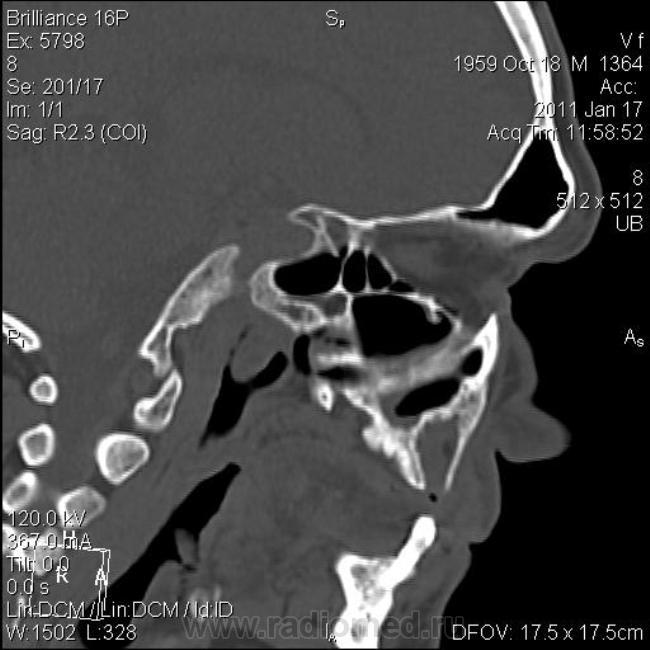

КТ головного мозга. Случайная находка. Жалоб "на челюсти" нет.

Мужчине 51 год. Периферический рак легкого. Очаговых изменений головного мозга не нашла. Пациент не критичен к своему состоянию (никуда не поеду, пусть как есть остается), поэтому отсутствие жалоб еще ничего не значит.

Контуры внутренние деструктивной полости изъеденные, кость вздута, но внешне не видно. В центре уровень?  с плотностью 30 ед.Н. Адамантинома? С зубными делами практически не сталкиваюсь. Нужна Ваша помощь. Какие будут идеи, уважаемые коллеги?

На мой взгляд процесс был, да прошел. Состояние после апикальной кисты удаленного зуба

Я думаю, это радикулярная киста с вторичным гиперостозом стенок воспалительного характера. Не уверен, что это состояние можно назвать остеомиелитом.

На метастаз и адамантиному непохоже.

До кабинета стоматолога дело не дошло. Просто триллер получился... пациент отказался от осмотра, мол, выписывают, как заболит - пойду в поликлинику. А когда пришел за диском с DICOM, у меня в ординаторской была стоматолог. Ей-богу случайно!)) Осмотрели ротовую полость. Хоромlaugh. Слизистая совершенно нормальная. Потом мы тем же хором его анамнестически "пытали" - каждое слово вытягивая словно клещами. Затащить в стомат.кресло не удалось, но вывод стоматолога после просмотра КТ таков - вероятнее всего, киста с периодическим нагноением.